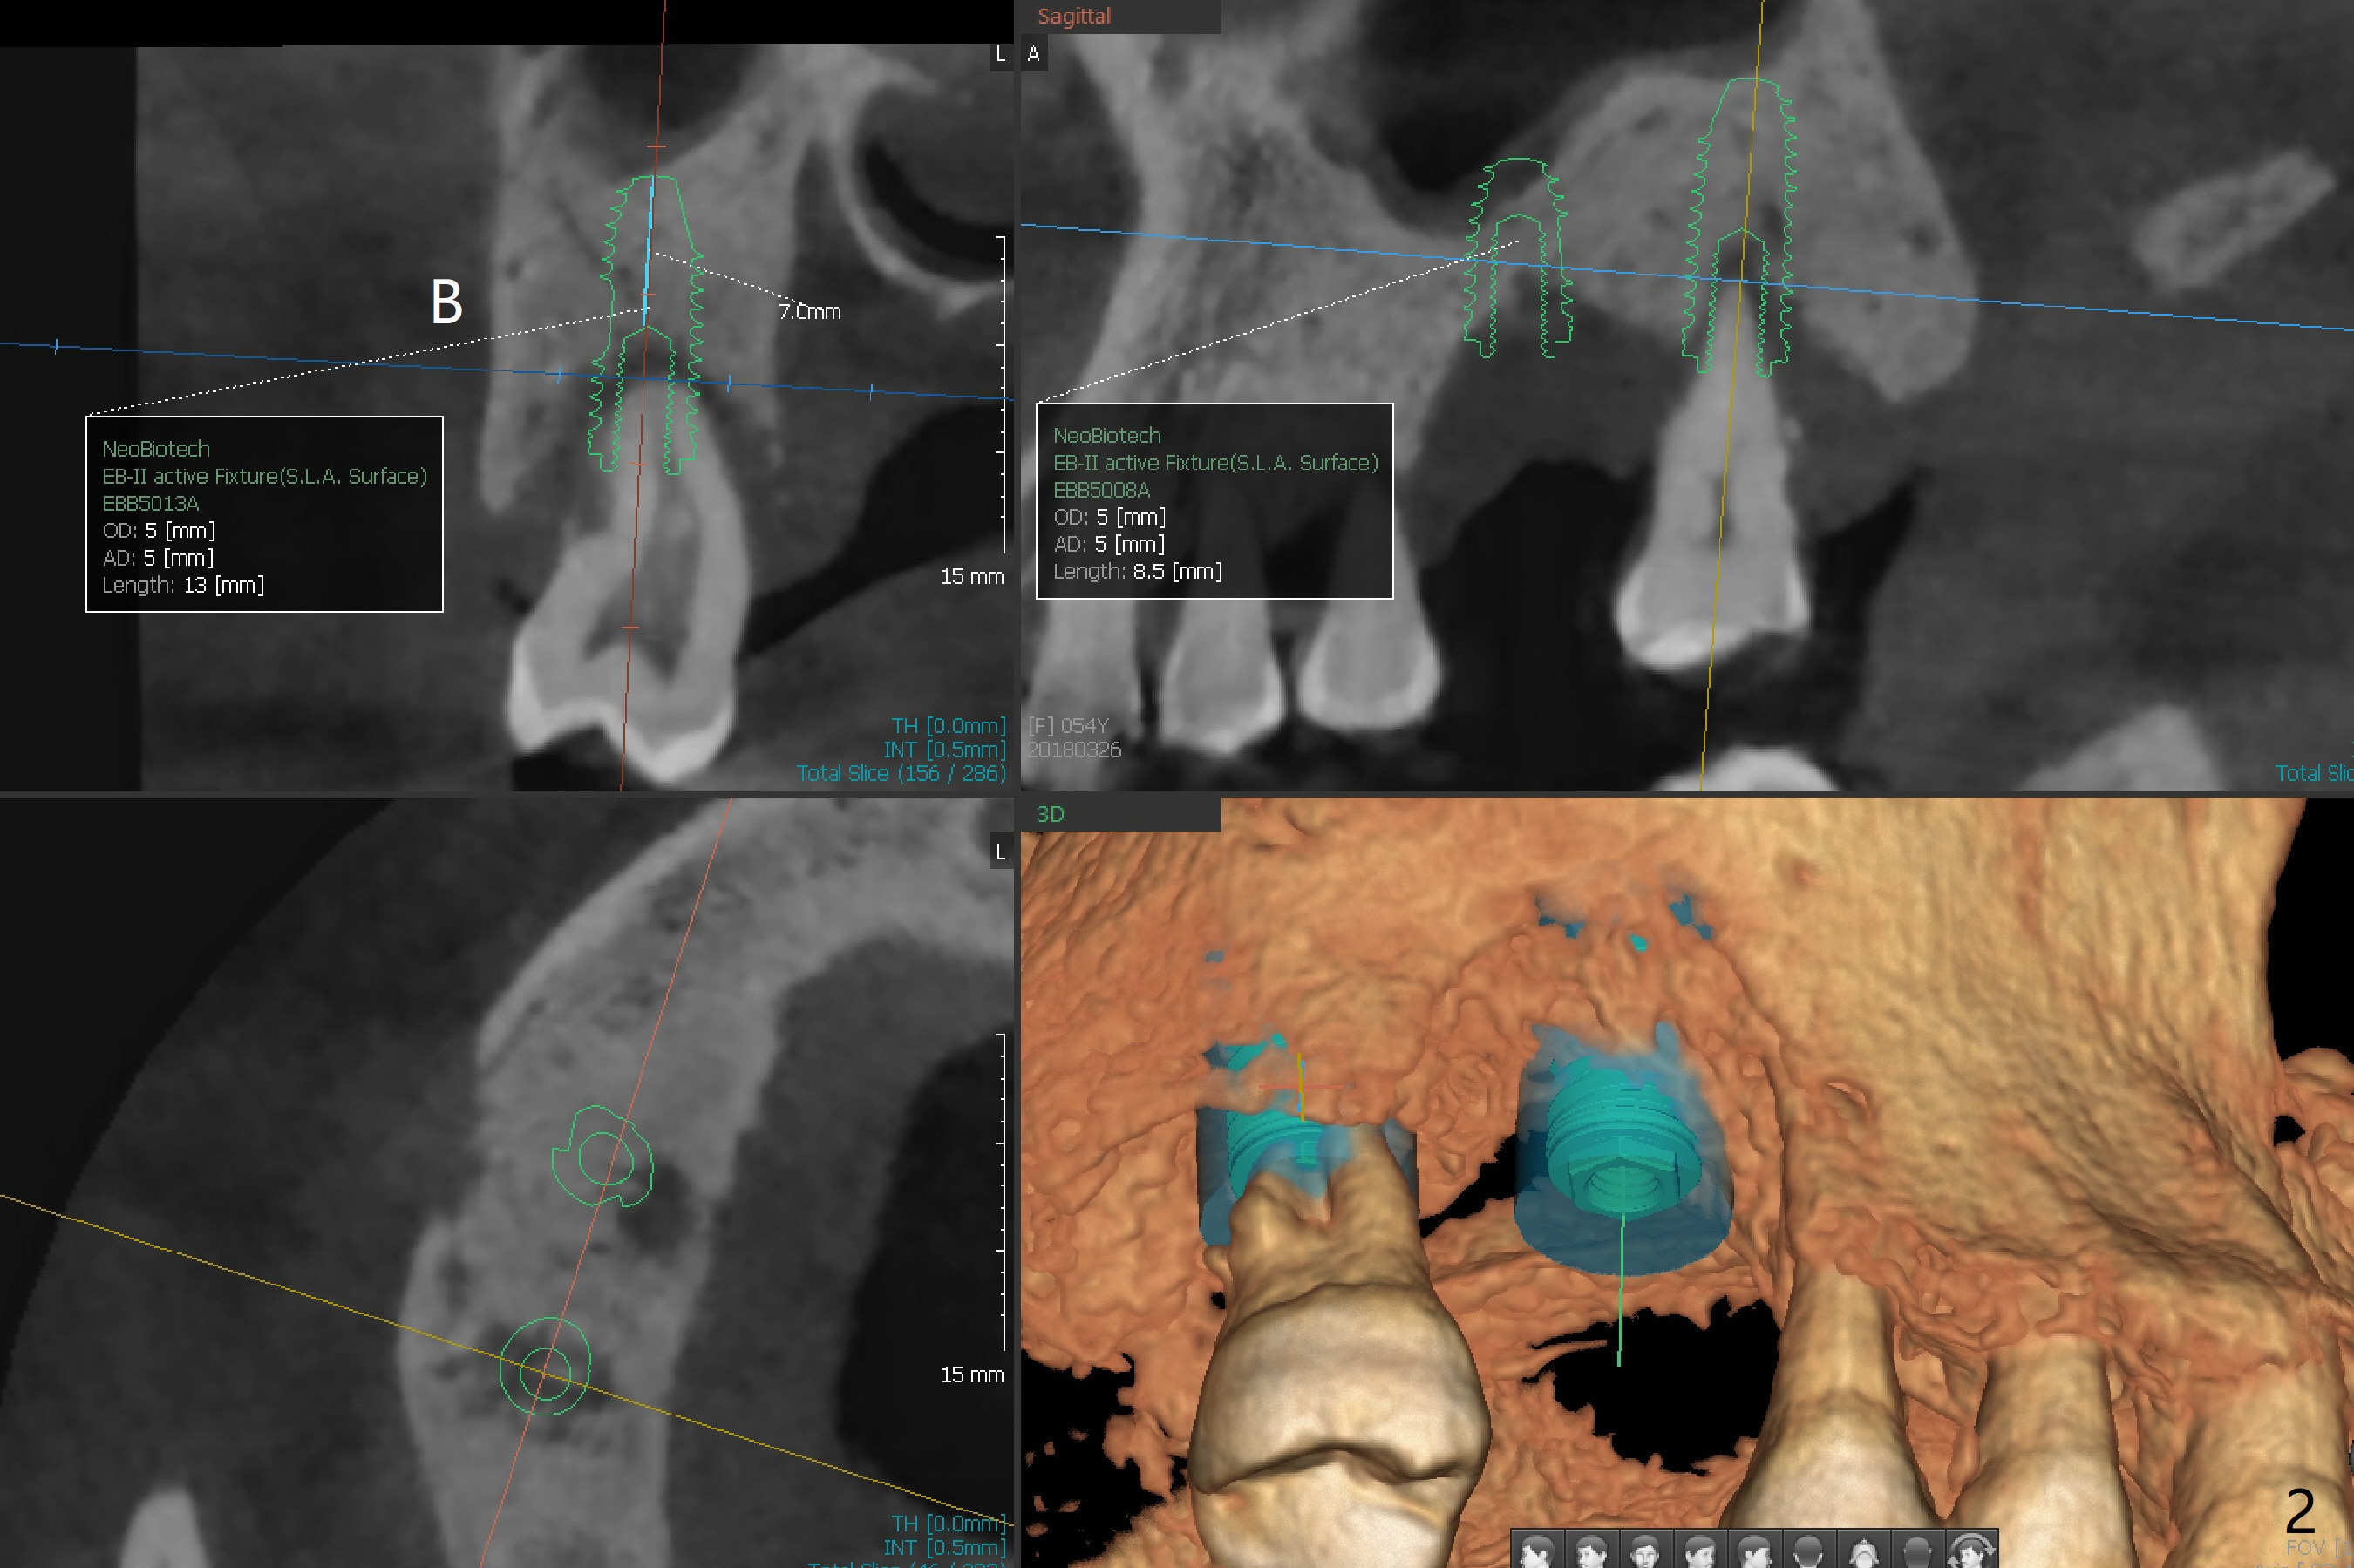

The tooth #2 of a 54-year-old woman has severe bone loss, while #3 has exfoliated (Fig.1). If the former is found without shifting, incision will be made at #3 (and prepare 4 and 6 mm tissue punches), followed by IS drills with 3 mm stoppers until 4.5 mm in diameter (Fig.3). Sinus lift will be accomplished with 3.6 mm round drill from Master Kit with 4-6 mm stoppers, followed by PRF membrane (total 3-4) and Vanilla Graft. Use Prosthetic Planning Kit to choose a proper cementation abutment. The tooth #2 will be extracted. Osteotomy starts with 7 mm stopper (Fig.2,3)...